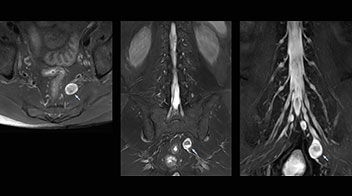

Distinguishing typical from atypical herniation informs the surgeon

“Although symptoms of typical disc herniation and atypical hernia are very similar, the actual site of herniation is different. It is therefore important to characterize the nerve’s condition both inside and outside of the intervertebral foramina. “Conversely, if we see no abnormality in NerveVIEW, we can assume at least that there is no severe condition that requires surgery. Like this, it can help us avoid unnecessary surgery. NerveVIEW can have a tremendous impact in this way.”

“NerveVIEW is really useful for those cases where a nerve disorder is strongly suspected based on the clinical examination but our regular MRI images do not show any findings. These atypical herniations and spinal canal stenosis, occurring in 5% to 15% of the total lumbar herniation/stenosis cases are our main target when using NerveVIEW,” says Dr. Yabuki.

"Because NerveVIEW helps us identify the actual hernia site, it can inform selection of the surgical approach"

“The intra-luminal signal of veins, especially around the intervertebral space, can be suppressed well with NerveVIEW. As a result, we can easily observe the detailed nerve structure around the posterior ganglion,” he says. “This is why we use 3D NerveVIEW for intraforaminal stenosis and extraforaminal stenosis/herniation (lateral disc herniation). On the other hand, if herniation is suspected to exist inside the dorsal root ganglion (DRG), balanced TFE or ProSet-FFE is applied. NerveVIEW is not suitable for evaluating the median type of herniation.” The SE-EPI DWI-based method for MR neurography works well for large FOV exams like whole-body MRI, but focal examination of nerves is often limited by the attainable spatial resolution (both inplane and slice direction) and geometric distortion. “3D NerveVIEW achieves higher in-plane resolution – close to our other routine spine sequences – and the source images can be used instead of adding a fat-suppressed T2-weighted sequence,” Tanji says.

“Recently, the two surgical methods extreme and oblique lateral interbody fusion (XLIF and OLIF) have become mainstream for minimally invasive treatment of lumbar spinal canal stenosis and intervertebral foramen stenosis. With these surgical techniques, the spine is approached from the flank, and prior knowledge of the exact anatomy of the lumbosacral plexus would be extremely helpful. To that end, high slice resolution (less than 1 mm acquisition) that enables sharper sagittal MPR images will be needed.”

“For both brachial and lumbar plexus, we are currently using a 230 mm FOV and voxels of about 1 x 1 x 2 mm acquired (1 x 1 x 1 mm reconstructed). This provides us a good representation of the nerves, even though this FOV is relatively small. Regarding the inplane resolution, we hope to be able to bring that down to 0.7 mm, similar to our typical 2D multislice T2W images,” says Tanji.